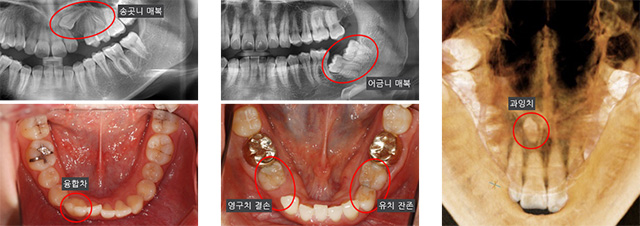

과거에 비해 현대인들에게서 부정교합의 비율이 증가한 것은 진화적 측면에서 그 원인을 찾을 수 있습니다. 가공되지 않아 질기고 딱딱한 음식을 섭취하던 과거와 달리 현대인의 식습관이 변화했으며, 그로 인해 질긴 음식을 주로 담당하던 치아가 퇴화하고 아래턱 크기가 감소하는 등의 변화가 나타났습니다. 이 결과로 매복치, 기형치, 과잉치, 맹출 장애 등 다양한 형태로 치아 맹출 이상이 나타납니다.

앞니가 고르지 않고 송곳니가 나지 않는 증상으로 내원한 12세 여학생입니다. 환자의 좌측 위 송곳니가 수평으로 매복되어 있었고 이로 인해 주변 치아 차이가 벌어진 상태였습니다. 발치를 하여 치료 기간을 줄이는 방법 대신, 자연치아를 유지할 수 있도록 간단한 수술을 통해 매복 치아에 치아교정 장치 부착하고 아래 쪽에는 교정용 스크류를 식립하여 치료를 진행하였습니다.

본래 송곳니가 있어야 할 자리로 매복된 송곳니를 이동시켰습니다. 그 결과 고르지 않았던 앞니가 가지런해졌으며 치아 사이에 공간이 생겼던 곳에 송곳니가 정상적으로 위치하게 되었습니다.

위 어금니가 바깥쪽으로 나 있어 식사 시 불편함을 호소한 13세 여학생입니다. 검진 결과 우측 위 어금니들이 정상적으로 나올 공간이 부족한 상태였으며 위 어금니가 아래 어금니와 닿지 않는 가위교합 증상을 확인했습니다. 또한 아래턱이 상대적으로 뒤쪽에 위치한 돌출입(골격성 2급 부정교합) 증상과 위/아래 앞니가 깊게 물리는 상태(과개교합) 등의 증상을 보여 이를 함께 개선하기 위해 양쪽 위 작은 어금니를 발치하고 치료를 진행하였습니다.

어금니가 정상적으로 자리를 잡지 못해 나타나던 불편함을 해소하였고 위/아래 전체 치아가 자연스럽게 맞물릴 수 있게 되었습니다.

왼쪽 위 치아들의 모양과 위치가 정상적이지 않았고 치열이 대칭적이지 않아 교정 치료를 권유 받고 내원한 학생입니다. 좌측 위 송곳니와 작은 어금니의 위치가 바뀌어 있고 우측 작은 어금니가 결손되어 주위 치아들이 기울어져 있으며 틈새가 벌어져 있습니다. 고정식 교정 장치를 이용하여 치열을 고르게 하고 결손된 치아 공간을 재배치하였습니다.

비대칭 모양의 치열을 대칭 형태로 개선하였고 송곳니와 작은 어금니의 위치를 정상적으로 되돌렸습니다. 또한 결손된 치아 위치는 성인이 된 후 임플란트를 식립할 수 있도록 유지 관리하였습니다.